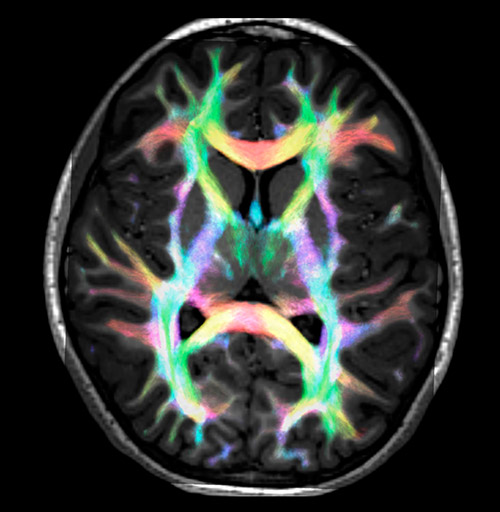

All images were created from the same acquisition in a child using Ingenia 3.0T CX and 32-channel dS Head coil. Diffusion data was acquired at b-values 0, 500, 1000, 2000, 3000. The use of high b-values (3000 s/mm2) effectively suppresses extra-axonal water signal and provides high angular resolution.

CSD of multishell DWI results in the white matter FOD at each voxel. Unlike the conventional diffusion tensor model, this approach enables accurate modeling of multiple fiber populations within a single voxel.

Crossings of the corpus callosum, corticospinal tracts, and the superior longitudinal fasciculus are shown.

Crossing fibers of the corpus callosum bordered by the superior longitudinal fasciculus as well as within in the pons.

Super-resolution directionally encoded color track-density imaging overlaid on T1-weighted structural MRI.